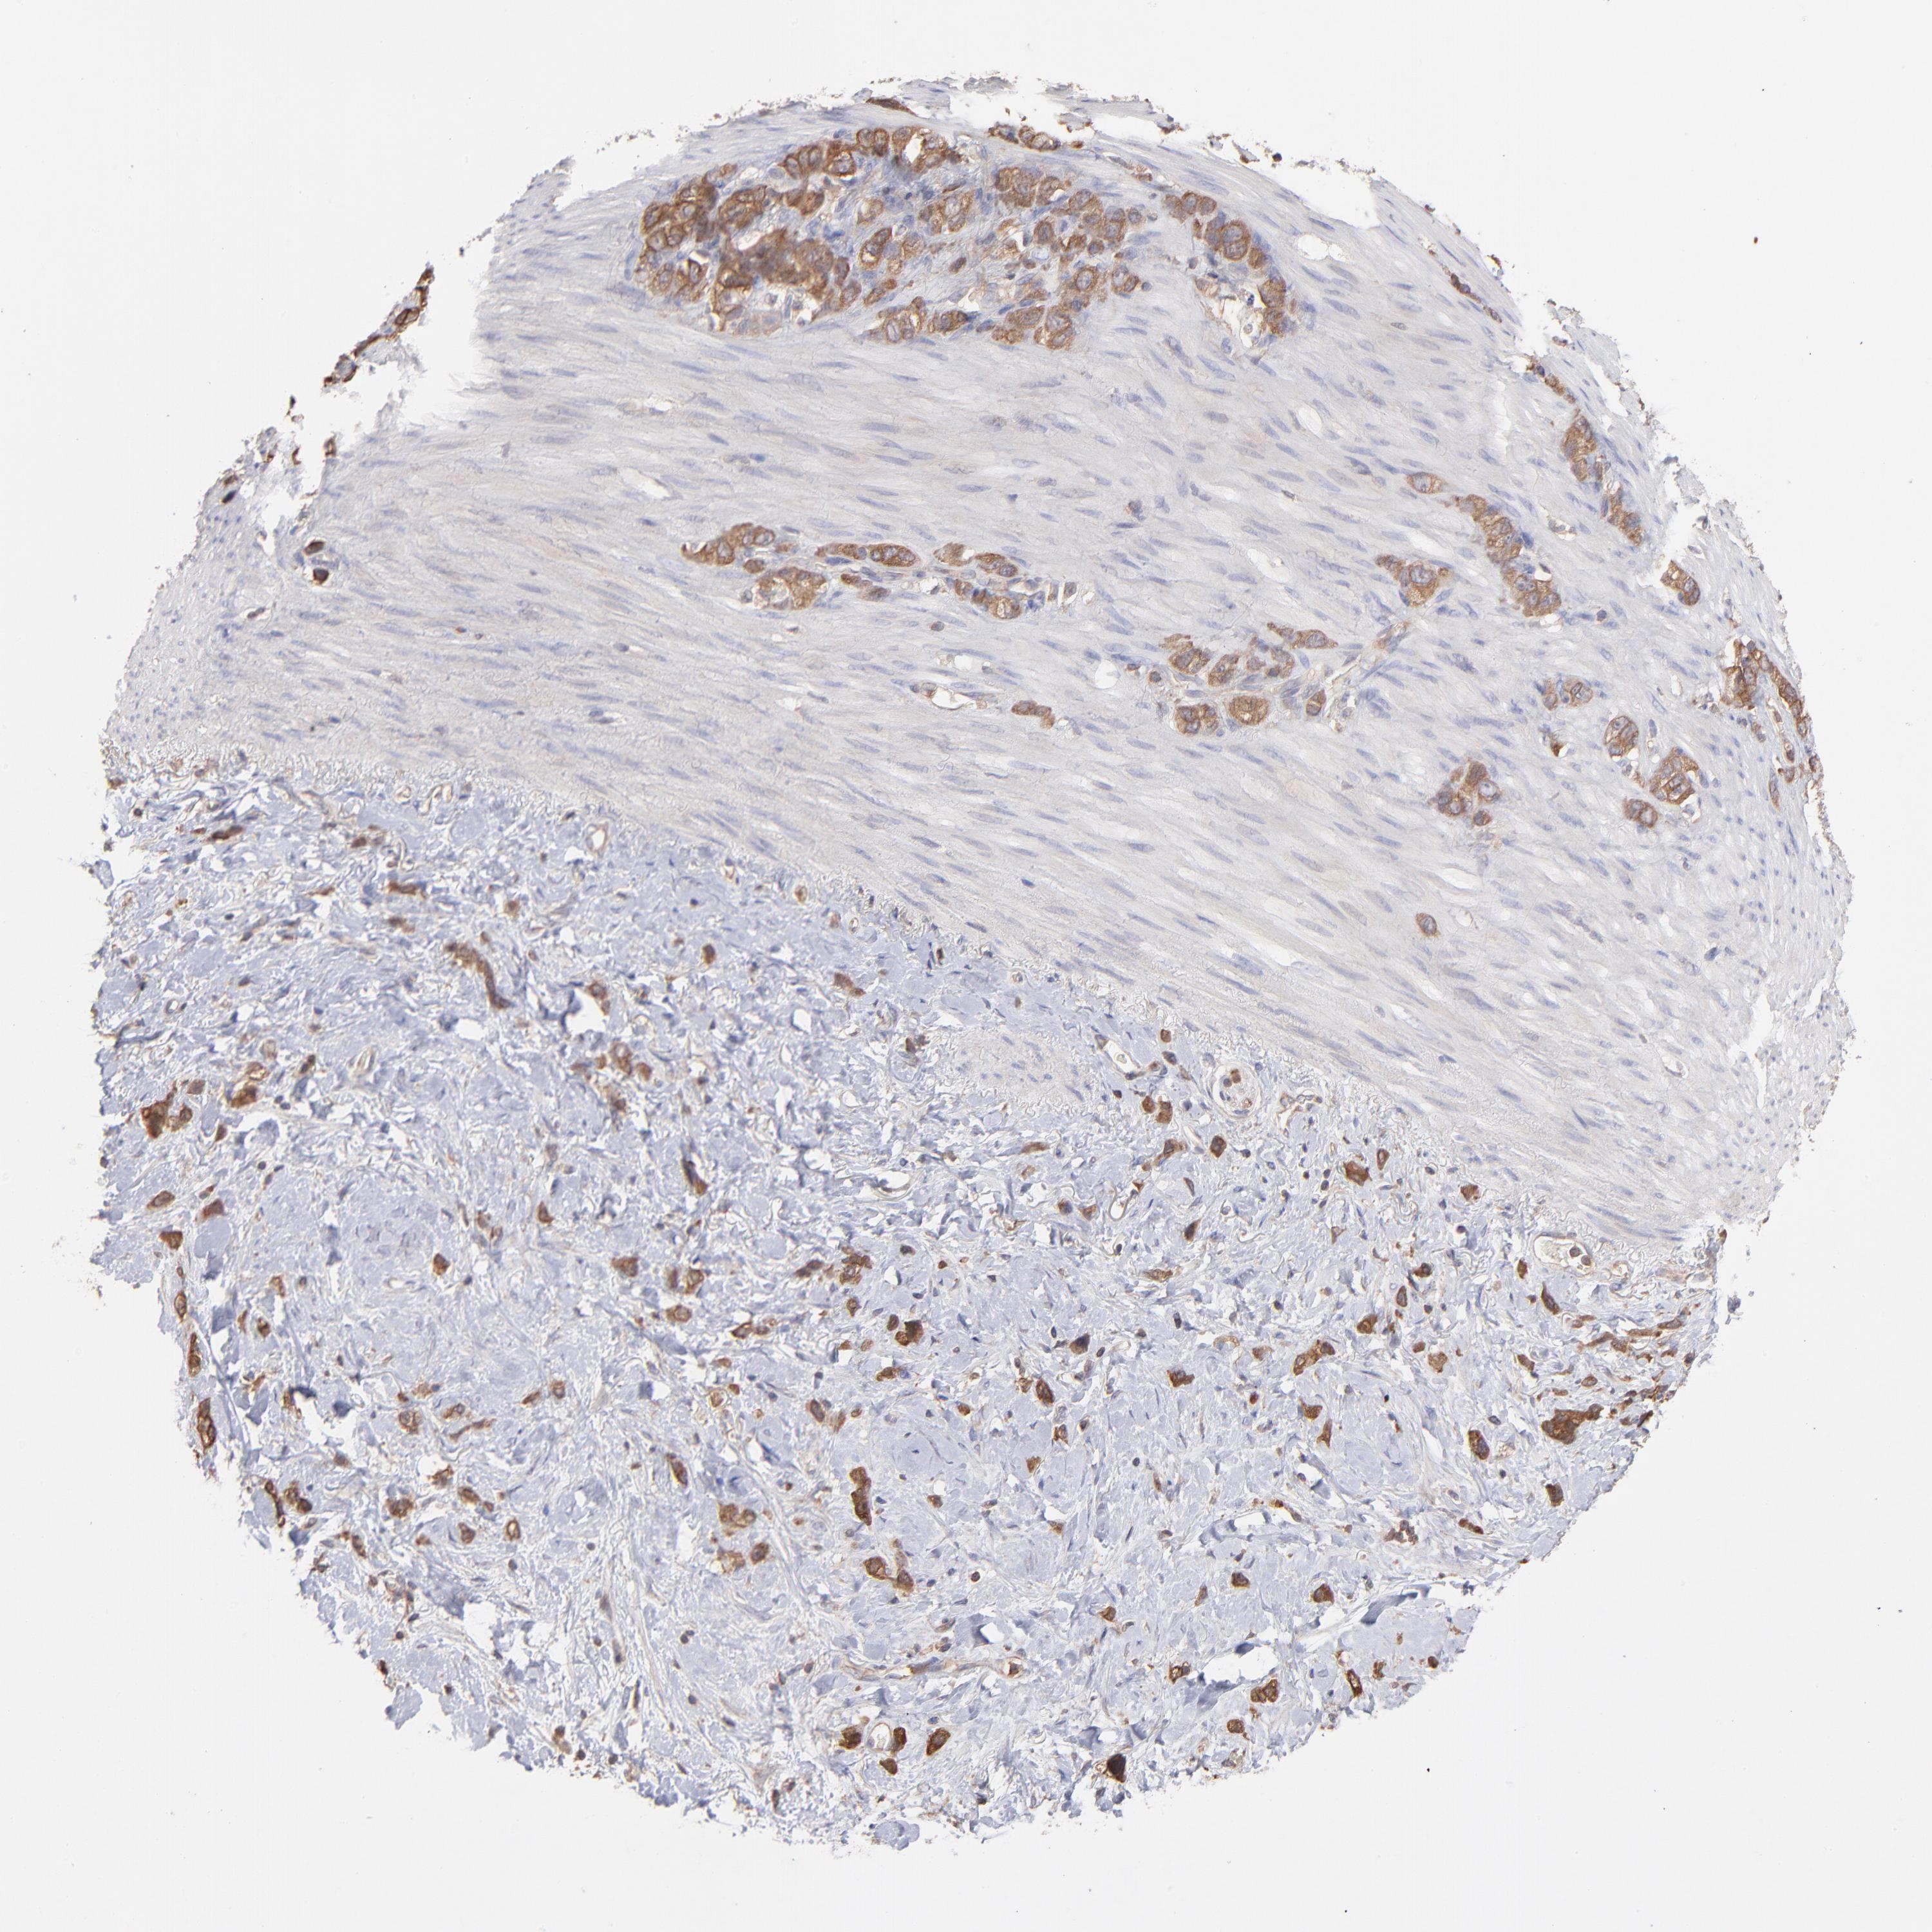

STOMACH CANCER - Protein expressioni

A mouse-over function shows sample information and annotation data. Click on an image to view it in a full screen mode. Samples can be filtered based on level of antibody staining by selecting one or several of the following categories: high, medium, low and not detected. The assay and annotation is described here.

Note that samples used for immunohistochemistry by the Human Protein Atlas do not correspond to samples in the TCGA dataset.

Antibody stainingi

Antibody staining in the annotated cell types in the current human tissue is reported as not detected, low, medium, or high, based on conventional immunohistochemistry profiling in selected tissues. This score is based on the combination of the staining intensity and fraction of stained cells.

Each image is clickable and will lead to virtual microscopy that enables deeper exploration of all samples and also displays staining intensity scores, fraction scores and subcellular localization as well as patient and tissue information for each sample.

Antibody HPA051993

Antibody CAB003835

Staining

High

Medium

Low

Not detected

Intensity

Strong

Moderate

Weak

Negative

Quantity

>75%

75%-25%

<25%

None

Location

Nuclear

Cytoplasmic/membranous

Cytoplasmic/membranous,nuclear

Adenocarcinoma, NOS

Adenocarcinoma, High grade